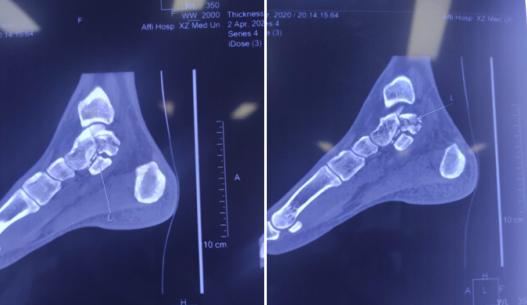

利用踝关节镜+骨科机器人,sararz足踝科完成踝关节韧带断裂合并骨折修复手术

33岁的肖先生,崴脚导致肿痛、淤青,难以下地,来到必威官方首页官网betway足踝科治疗。检查结果患者左距骨骨折,三角韧带、距腓前韧带、跟腓韧带损伤,需要做韧带修复和骨折复位手术。

讨论后,石荣剑副院长徐明亮主任手术团队为患者进行了关节镜下韧带修复术和机器人辅助下骨折固定术。首先利用踝关节镜探查距腓前韧带断裂,用可吸收带线锚钉修复;镜下探查复位保证距骨关节面平整;机器人定位,闭合平行打入两枚空心螺钉,骨折固定精准稳定。

该手术也是我省首次利用踝关节镜和骨科机器人完成的足踝关节韧带撕裂合并骨折修复手术,该微创手术既缩短了手术时间和术后恢复期,也降低了并发症发生率,效果很好,患者满意度更高。

术前CT

韧带受伤

右外踝骨折(左),术中(右)